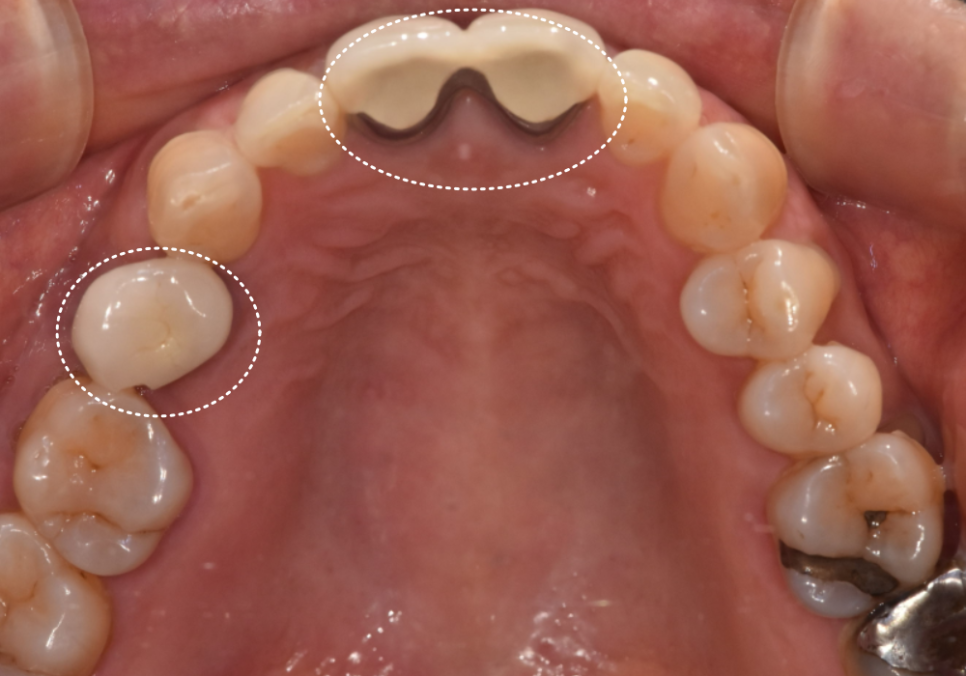

최종 보철 제작

잇몸 까매짐 원인,증상,치료 방법

4개월 후 임플란트가 뼈와 잘 유착되었는지

확인하기 위해 기계로 수치를 재어본 뒤

높은 수치가 나온 것을 확인하고

보철을 제작하기 위해 본을 뜹니다.

저희 병원은 원내 기공실이 있어서

보철 제작 과정에서 미세한 부분들을

즉시 조정하고 소통할 수 있기 때문에

외부 기공소로 보낼 때보다

색상이나 형태 재현도가 훨씬 정확합니다.

250906

특히 앞니는 자연광에서 봤을 때

주변 치아와 자연스럽게 어우러져야 하는데

사진만으로는 미세한 색 차이를

구현하기 어렵거든요.

250919

이후 최종 보철물을 제작해서 부착했고,

환자분은 잇몸 색도 자연스럽게 회복되고

냄새도 사라졌다고 하셨습니다.